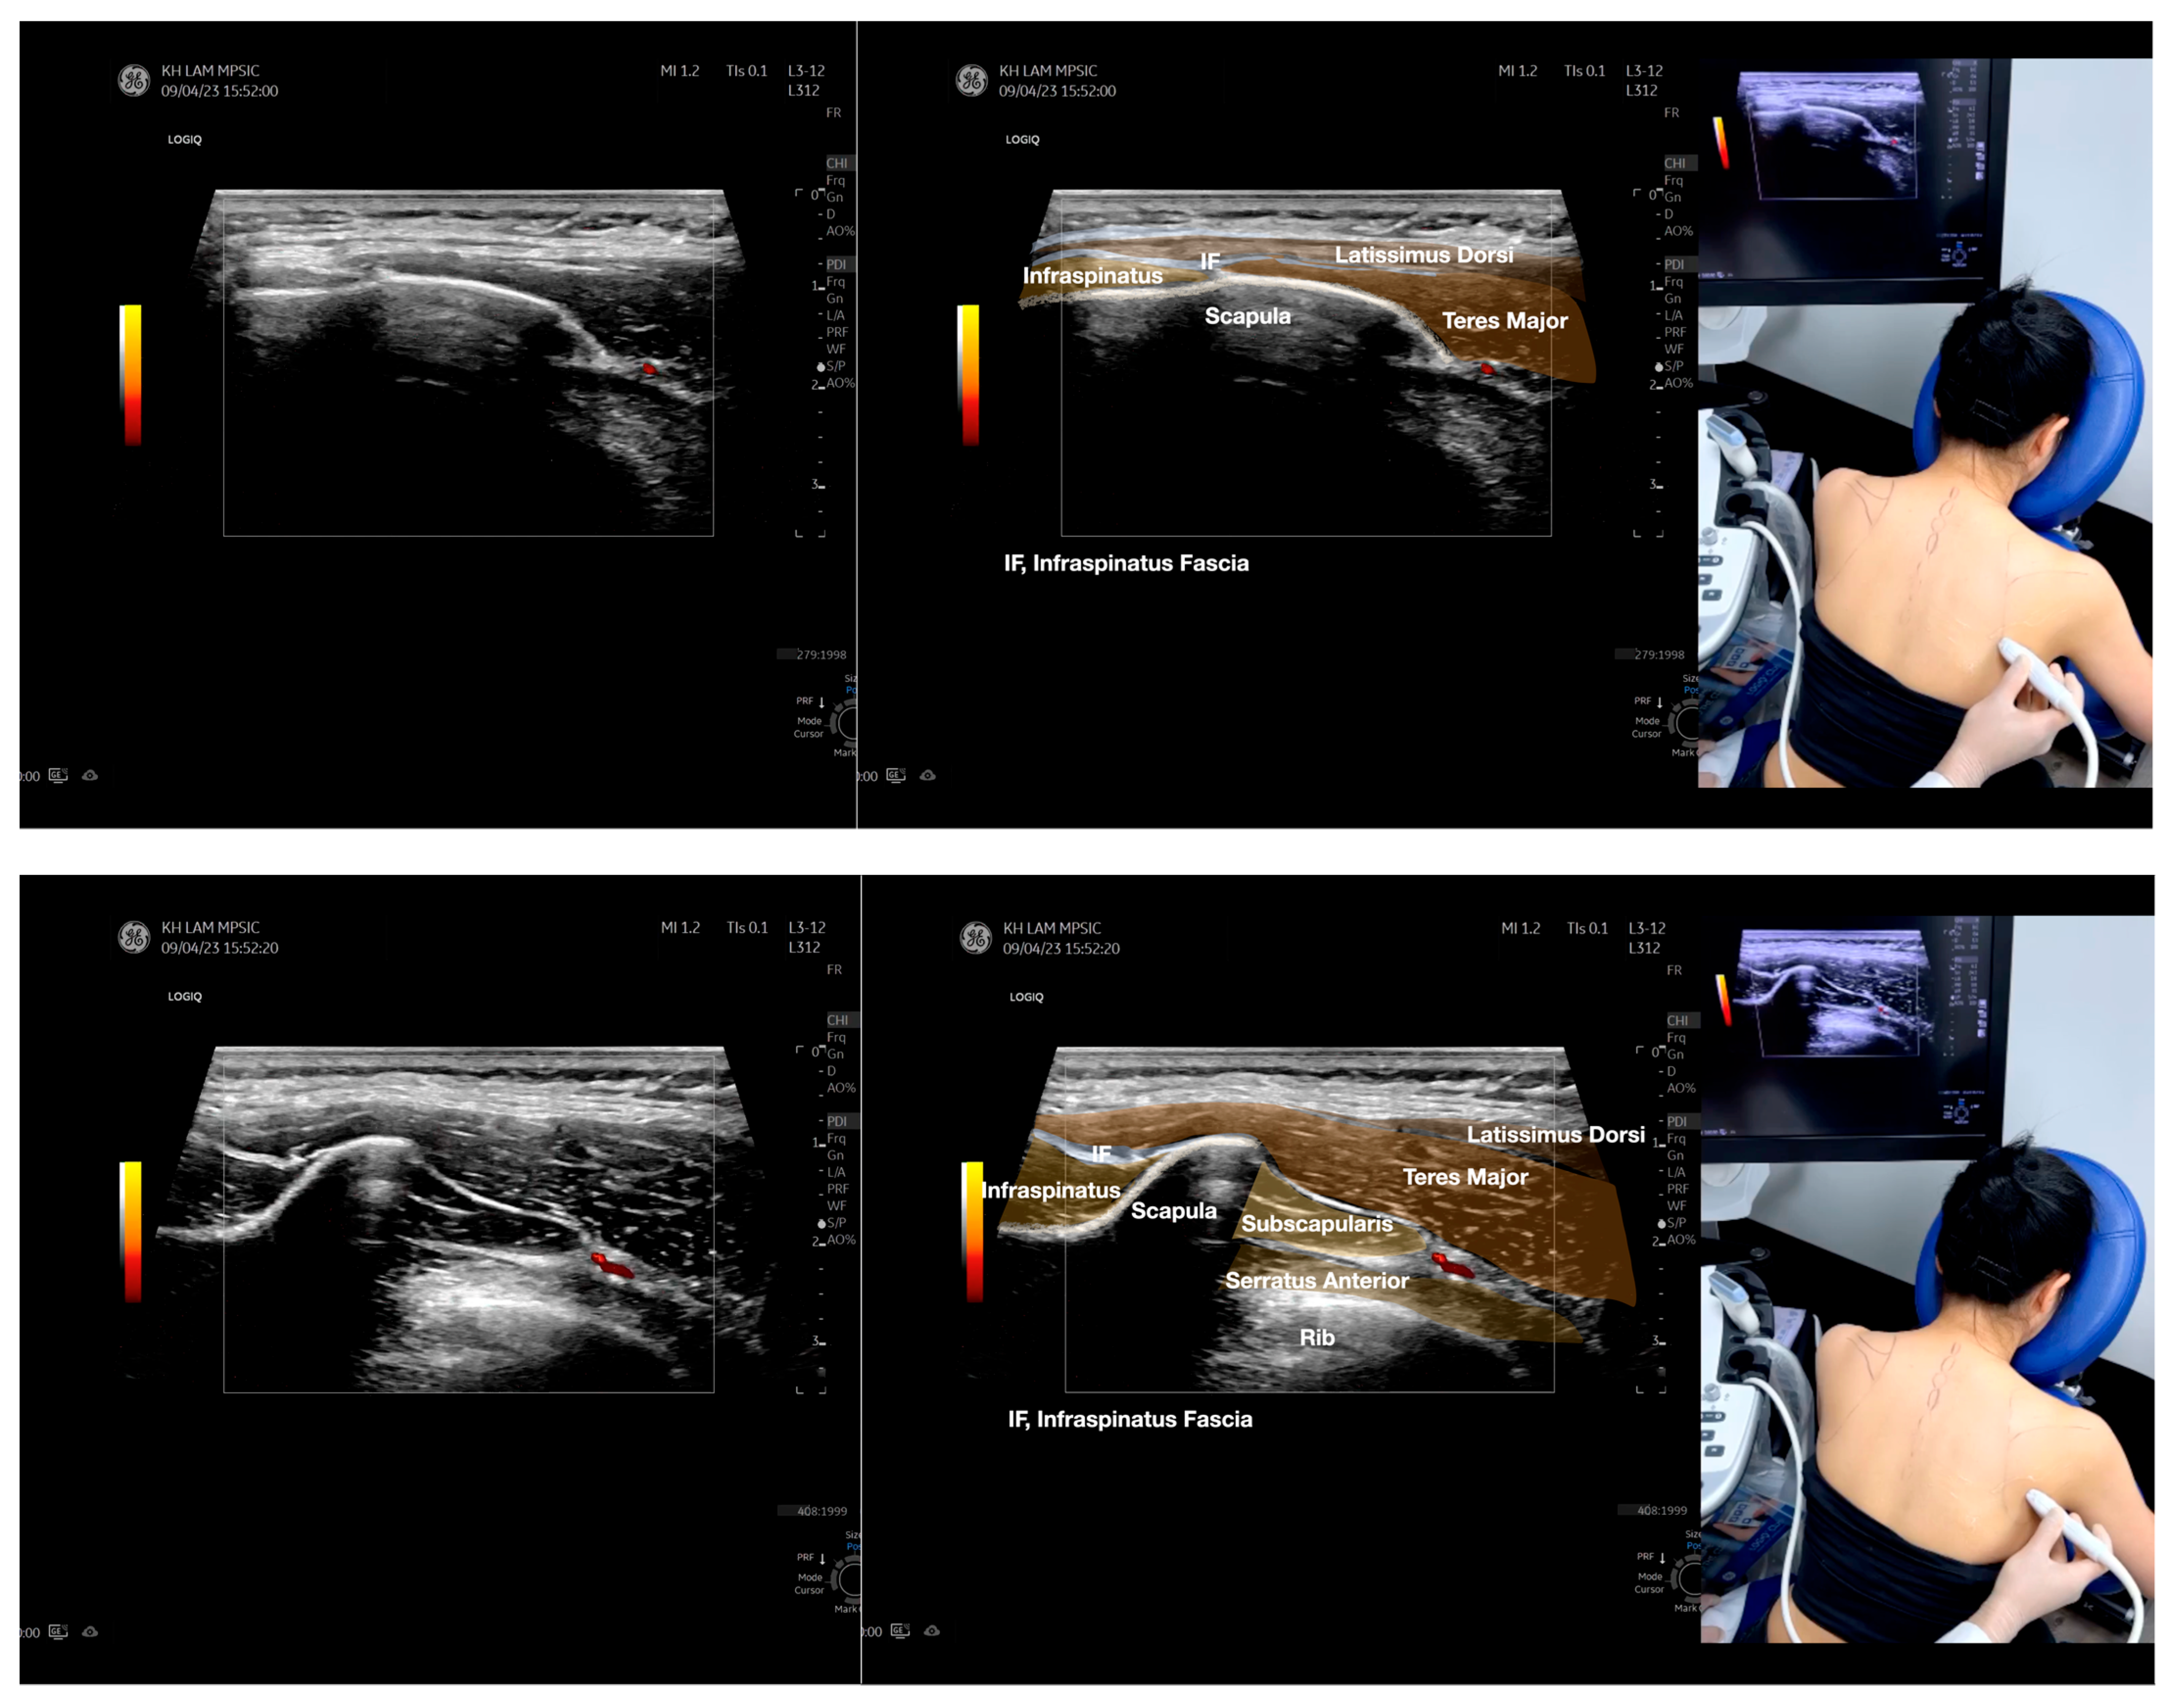

Figure 4.

Sonoanatomy of the medial edge of the scapula, its related muscles, and the infraspinatus fascia. The step-by-step scanning techniques of these structures illustrated in this figure have been shown in Video S8. Available online: https://www.dropbox.com/s/iaej3rxhl83kqt4/Figure%204.docx?dl=0 (accessed on 1 January 2023).